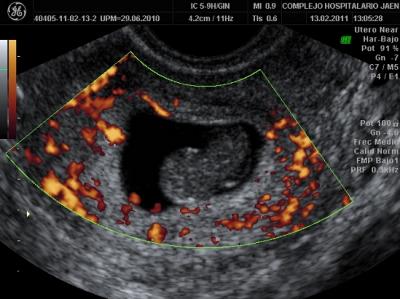

For the purpose of this study, 265 pregnant women participated in the tests. From these 265 women, 132 had suffered a spontaneous miscarriage during that year. The rest (other 133) were women with evolutionary pregnancy, selected among pregnant women attending an scheduled birth control appointment. All of them underwent an ultrasound examination, and were taken a blood sample for laboratory tests. Additionally, they were asked to answer a questionnaire. In total, 131 variables were assessed from each participant.